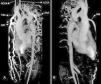

Three-dimensional volume rendering magnetic resonance angiography images: (A) left posterior oblique view and (B) right posterior oblique view, showing interruption of the descending aorta after the branching of the left subclavian artery. IA: interrupted aorta; IMA: internal mammary artery; LCCA: left common carotid artery; LSCA: left subclavian artery; RCCA: right common carotid artery; TrBc: truncus brachiocephalicus.

A 22-year-old man was referred to our cardiology department for investigation of hypertension. At presentation his blood pressure was 170/100 mmHg in both arms, and heart rate was 74 beats/min. The pulses were equal over both upper extremities, but bilateral femoral and popliteal pulses were extremely weak and the dorsalis pedis and anterior tibial pulses were not palpable. His past history was unremarkable except for hypertension. There was a II/VI systolic ejection murmur in the left second intercostal area and left scapular region in the back. Transthoracic echocardiography showed concentric left ventricular hypertrophy with normal ventricular function. Magnetic resonance (MR) angiography showed interruption of the descending aorta after the branching of the left subclavian artery (Figure 1). Dilated intercostal, intramammary and thoracodorsal arteries with accompanying anastomosis between the intercostal and thoracodorsal arteries were observed (Figure 2).